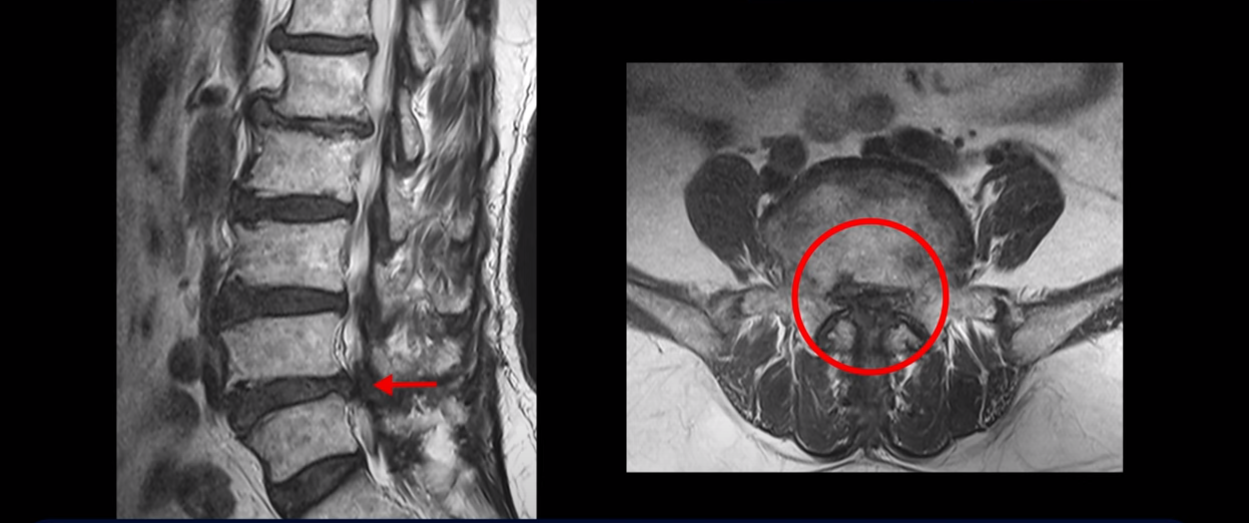

이분 MRI를 보면 척추의 여러 마디가 퇴행이 진행되어 안 좋습니다.

특히 4번 5번 마디가 제일 안 좋은데 보시다시피, 하얗게 보여야 될 신경이 거의 안 보일 정도로 척추관이 좁아져 있습니다.

이분은 허리도 아프지만 왼쪽 엉덩이와 다리가 너무 심하게 저리고 아팠는데 역시나 왼쪽 신경 가지가 빠져나가는 구멍이 막혀 있어서 매우 어둡게 보입니다.